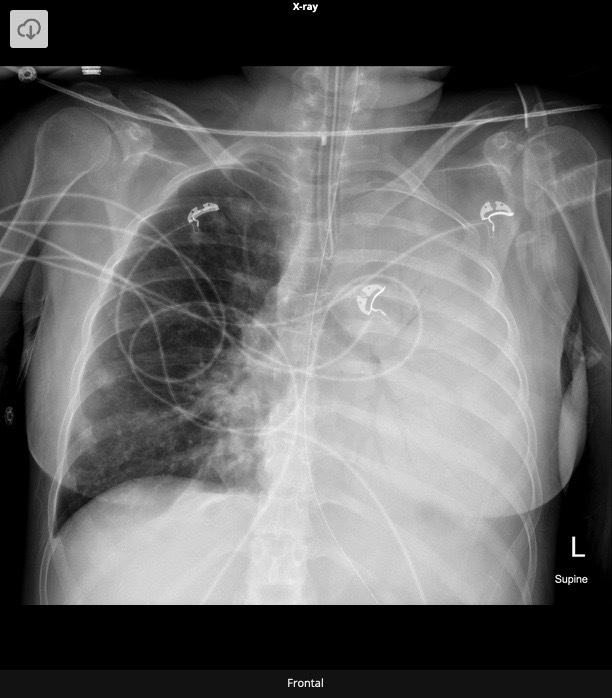

20.1 What is the abnormality in this CXR?

a. Pneumonectomy

b. Pleural effusion

c. Pneumonia

d. Unilateral pulmonary oedema

A

Complete white-out of left lung with air bronchogram sign consistent with total consolidation. Patchy areas of ground glass opacities in right lung. There is silhouetting of the left heart border and left hemi-diaphragm. There is no rib crowding to suggest atelectasis.

Complete white-out of the hemithorax with air bronchograms and trachea in a central position is consistent with consolidation secondary to pneumonia. The patient is on linezolid, micafungin, and piperacillin-tazobactam pending culture and susceptibility studies.

Differential diagnosis of hemithorax white-out with a midline trachea include:

- consolidation

- pulmonary edema/ARDS

- pleural mass

- chest wall mass